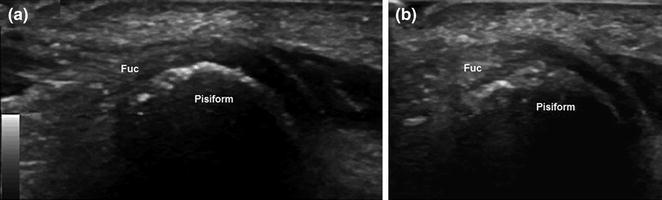

Энтезит локтевого сгибателя запястья. a Сагиттальные и аксиальные проекции, b Ультразвуковое исследование показывает увеличенное гипоэхогенное сухожилие локтевого сгибателя запястья (Fuc), с небольшими кальцификатами и кортикальными повреждениями гороховидной кости.

Сухожилие локтевого сгибателя запястья отделено от гороховидной кости бурсой, которая видна на УЗИ только тогда, когда в ней содержится жидкость. По причинам возникновения бурсит на этом уровне аналогичен бурситу в других регионах: в большинстве случаев он обусловлен микротравмами или связан с воспалительными заболеваниями.

Гороховидная бурса. а Сагиттальное и аксиальное наблюдение, б УЗ-сканирование. Небольшая гороховидная бурса (стрелки), расположенная между сухожилием локтевого сгибателя запястья (Fuc) и гороховидной костью, становится видимой на УЗИ при наличии жидкости.